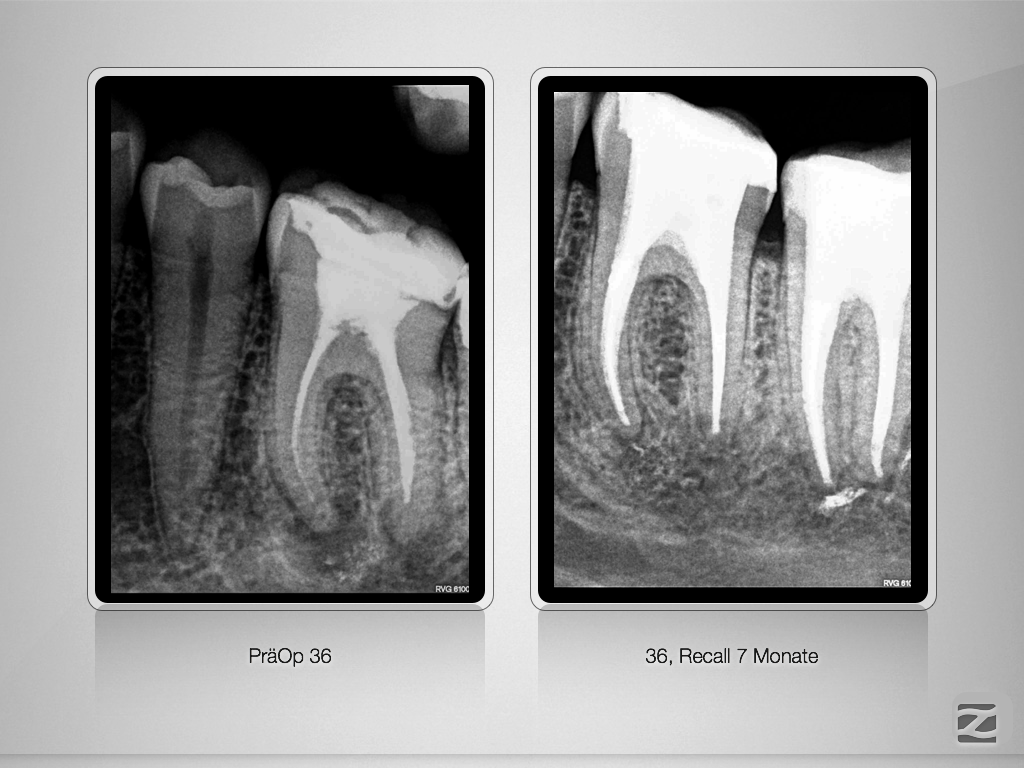

Ausgedehnte apikale Lyse